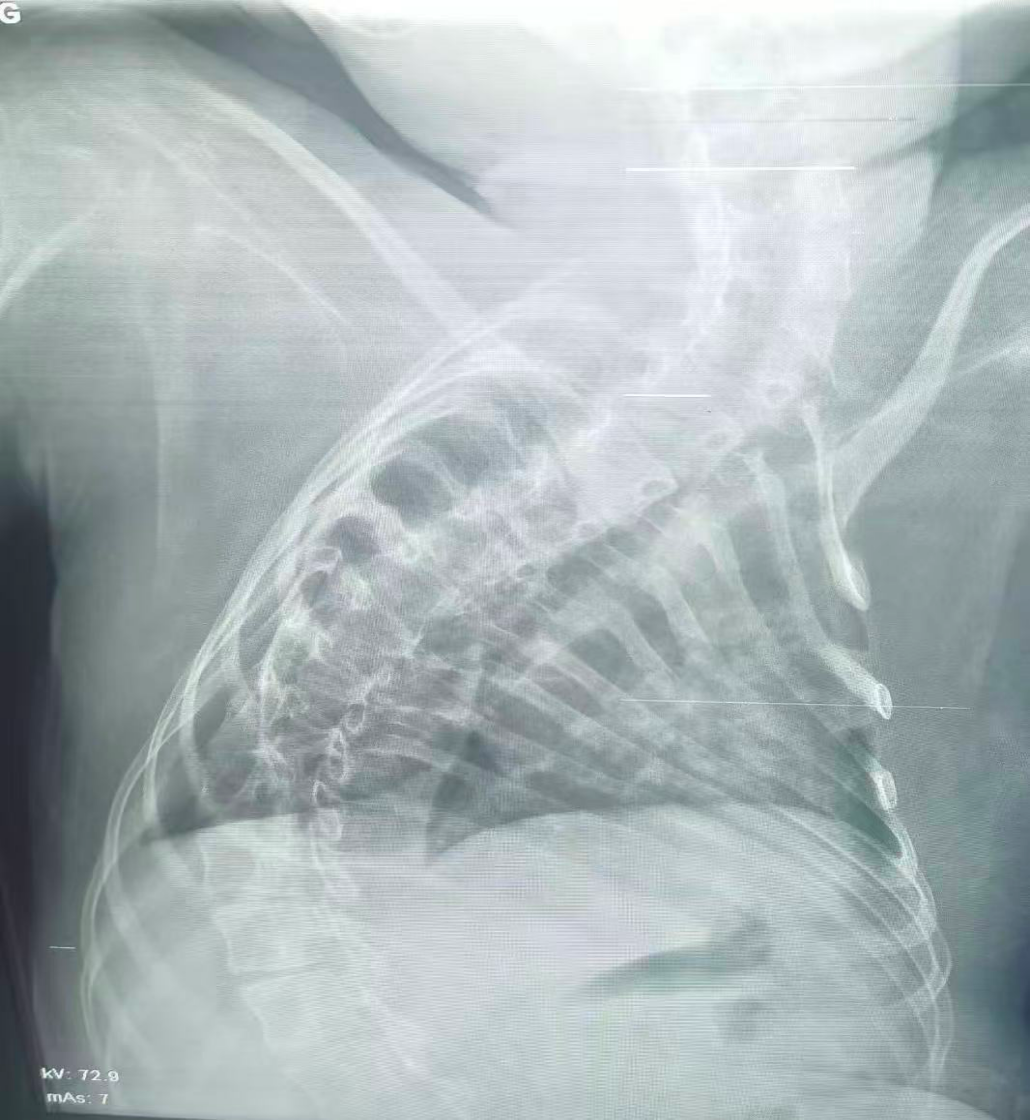

治療前

該患兒因患脊髓性肌萎縮癥長(zhǎng)期臥床,呼吸肌已嚴(yán)重?zé)o力,自主呼吸微弱且?guī)缀鯁适Э人耘盘的芰?,此次并發(fā)支氣管肺炎后,肺部感染迅速加重,生命已然懸于一線。更棘手的是,嚴(yán)重的脊柱側(cè)彎使患兒胸廓畸形、氣道解剖結(jié)構(gòu)明顯移位,常規(guī)纖支鏡進(jìn)鏡路徑完全失效,扭曲狹窄的氣道如同縱橫交錯(cuò)的“迷宮”,每一步操作都必須精準(zhǔn)到毫米級(jí)別。

體位擺放則成為另一道“攔路虎”,既要滿足纖支鏡操作需求,又要避免側(cè)彎脊柱受壓、防止肌萎縮引發(fā)關(guān)節(jié)脫位,每個(gè)角度都得反復(fù)測(cè)算。同時(shí),還需直面層層疊加的術(shù)中危機(jī):因患兒呼吸肌功能幾乎喪失,纖支鏡占用狹窄氣道空間后,缺氧、二氧化碳潴留及急性呼吸衰竭、心跳驟停風(fēng)險(xiǎn)陡增;灌洗過(guò)程中若液體殘留將加重肺部感染,而患兒免疫力低下,導(dǎo)致敗血癥的風(fēng)險(xiǎn)顯著升高。